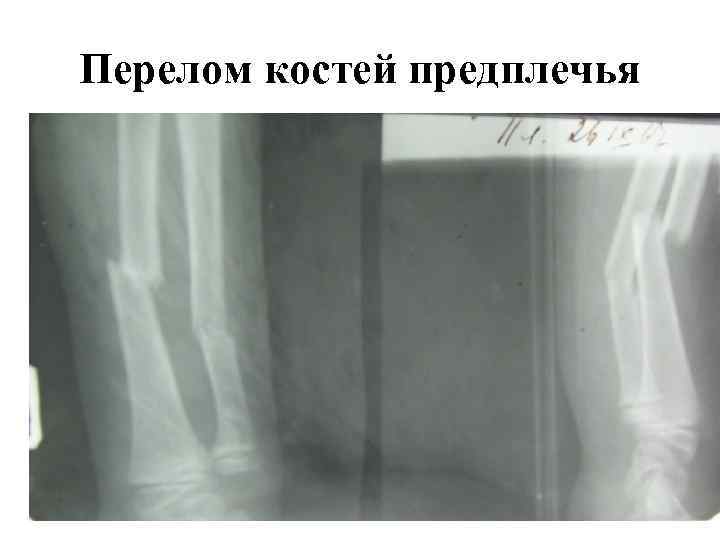

Рентгенологические признаки перелома кости 1. Плоскость перелома; 2. Смещение костных отломков

Плоскость перелома на рентгенограмме может выглядеть как линия просветления или линия затемнения. Это зависит от положения отломков. Если между отломками есть расстояние (диастаз), то плоскость перелома визиализируется как полоса просветления. Если произошло вклинение отломков или произошла интерпозиция отломков (наложение тени отломков при их захождении друг за друга) плоскость перелома выглядит как полоса затемнения.

Смещение отломков может быть по длине с захождением и расхождением их, по ширине (боковое), под углом, по оси ()ротационное или винтообразное).

Виды смещения костных отломков

Перелом костей предплечья